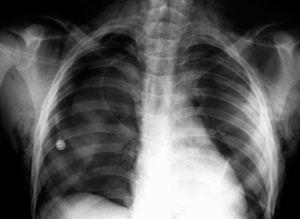

Varón de 12 años de edad, sin antecedentes personales de interés, que acudió al servicio de urgencias tras golpearse en la región cervical anterior con el manillar de una bicicleta. En la exploración física, el paciente presentaba dificultad respiratoria moderada y enfisema subcutáneo cervicotorácico que se extendía hasta el escroto. La radiografía de tórax confirmó la presencia de aire en el tejido subcutáneo y, además, puso de manifiesto un neumotórax derecho y un neumomediastino (fig. 1). Ante la sospecha de rotura de la vía aérea se realizó, a continuación, una broncoscopia flexible en quirófano y bajo anestesia general. Se observó una laceración profunda en la parte posterior membranosa traqueal de aproximadamente 2,5 cm de longitud (fig. 2). Esta lesión se encontraba a 5 cm de cuerdas vocales y a 7 cm de la carina aproximadamente. El resto del árbol traqueobronquial era normal. Dado el tamaño de la laceración y la sintomatología del paciente fue intervenido quirúrgicamente sin más demora. Se efectuó el cierre de la herida traqueal con sutura discontinua mediante un abordaje cervical anterior. Se comprobó intraoperatoriamente, mediante broncoscopia, el cierre completo de la laceración. El paciente fue extubado en el quirófano y la evolución postoperatoria cursó sin incidencias, y fue dado de alta una semana después de la intervención. La broncoscopia de control, a los 2 meses, fue normal y el paciente se encuentra actualmente asintomático con un seguimiento de 2 años.

Figura 1. Laceración traqueal en la que se observa el neumotórax, el neumomediastino y el enfisema subcutáneo.